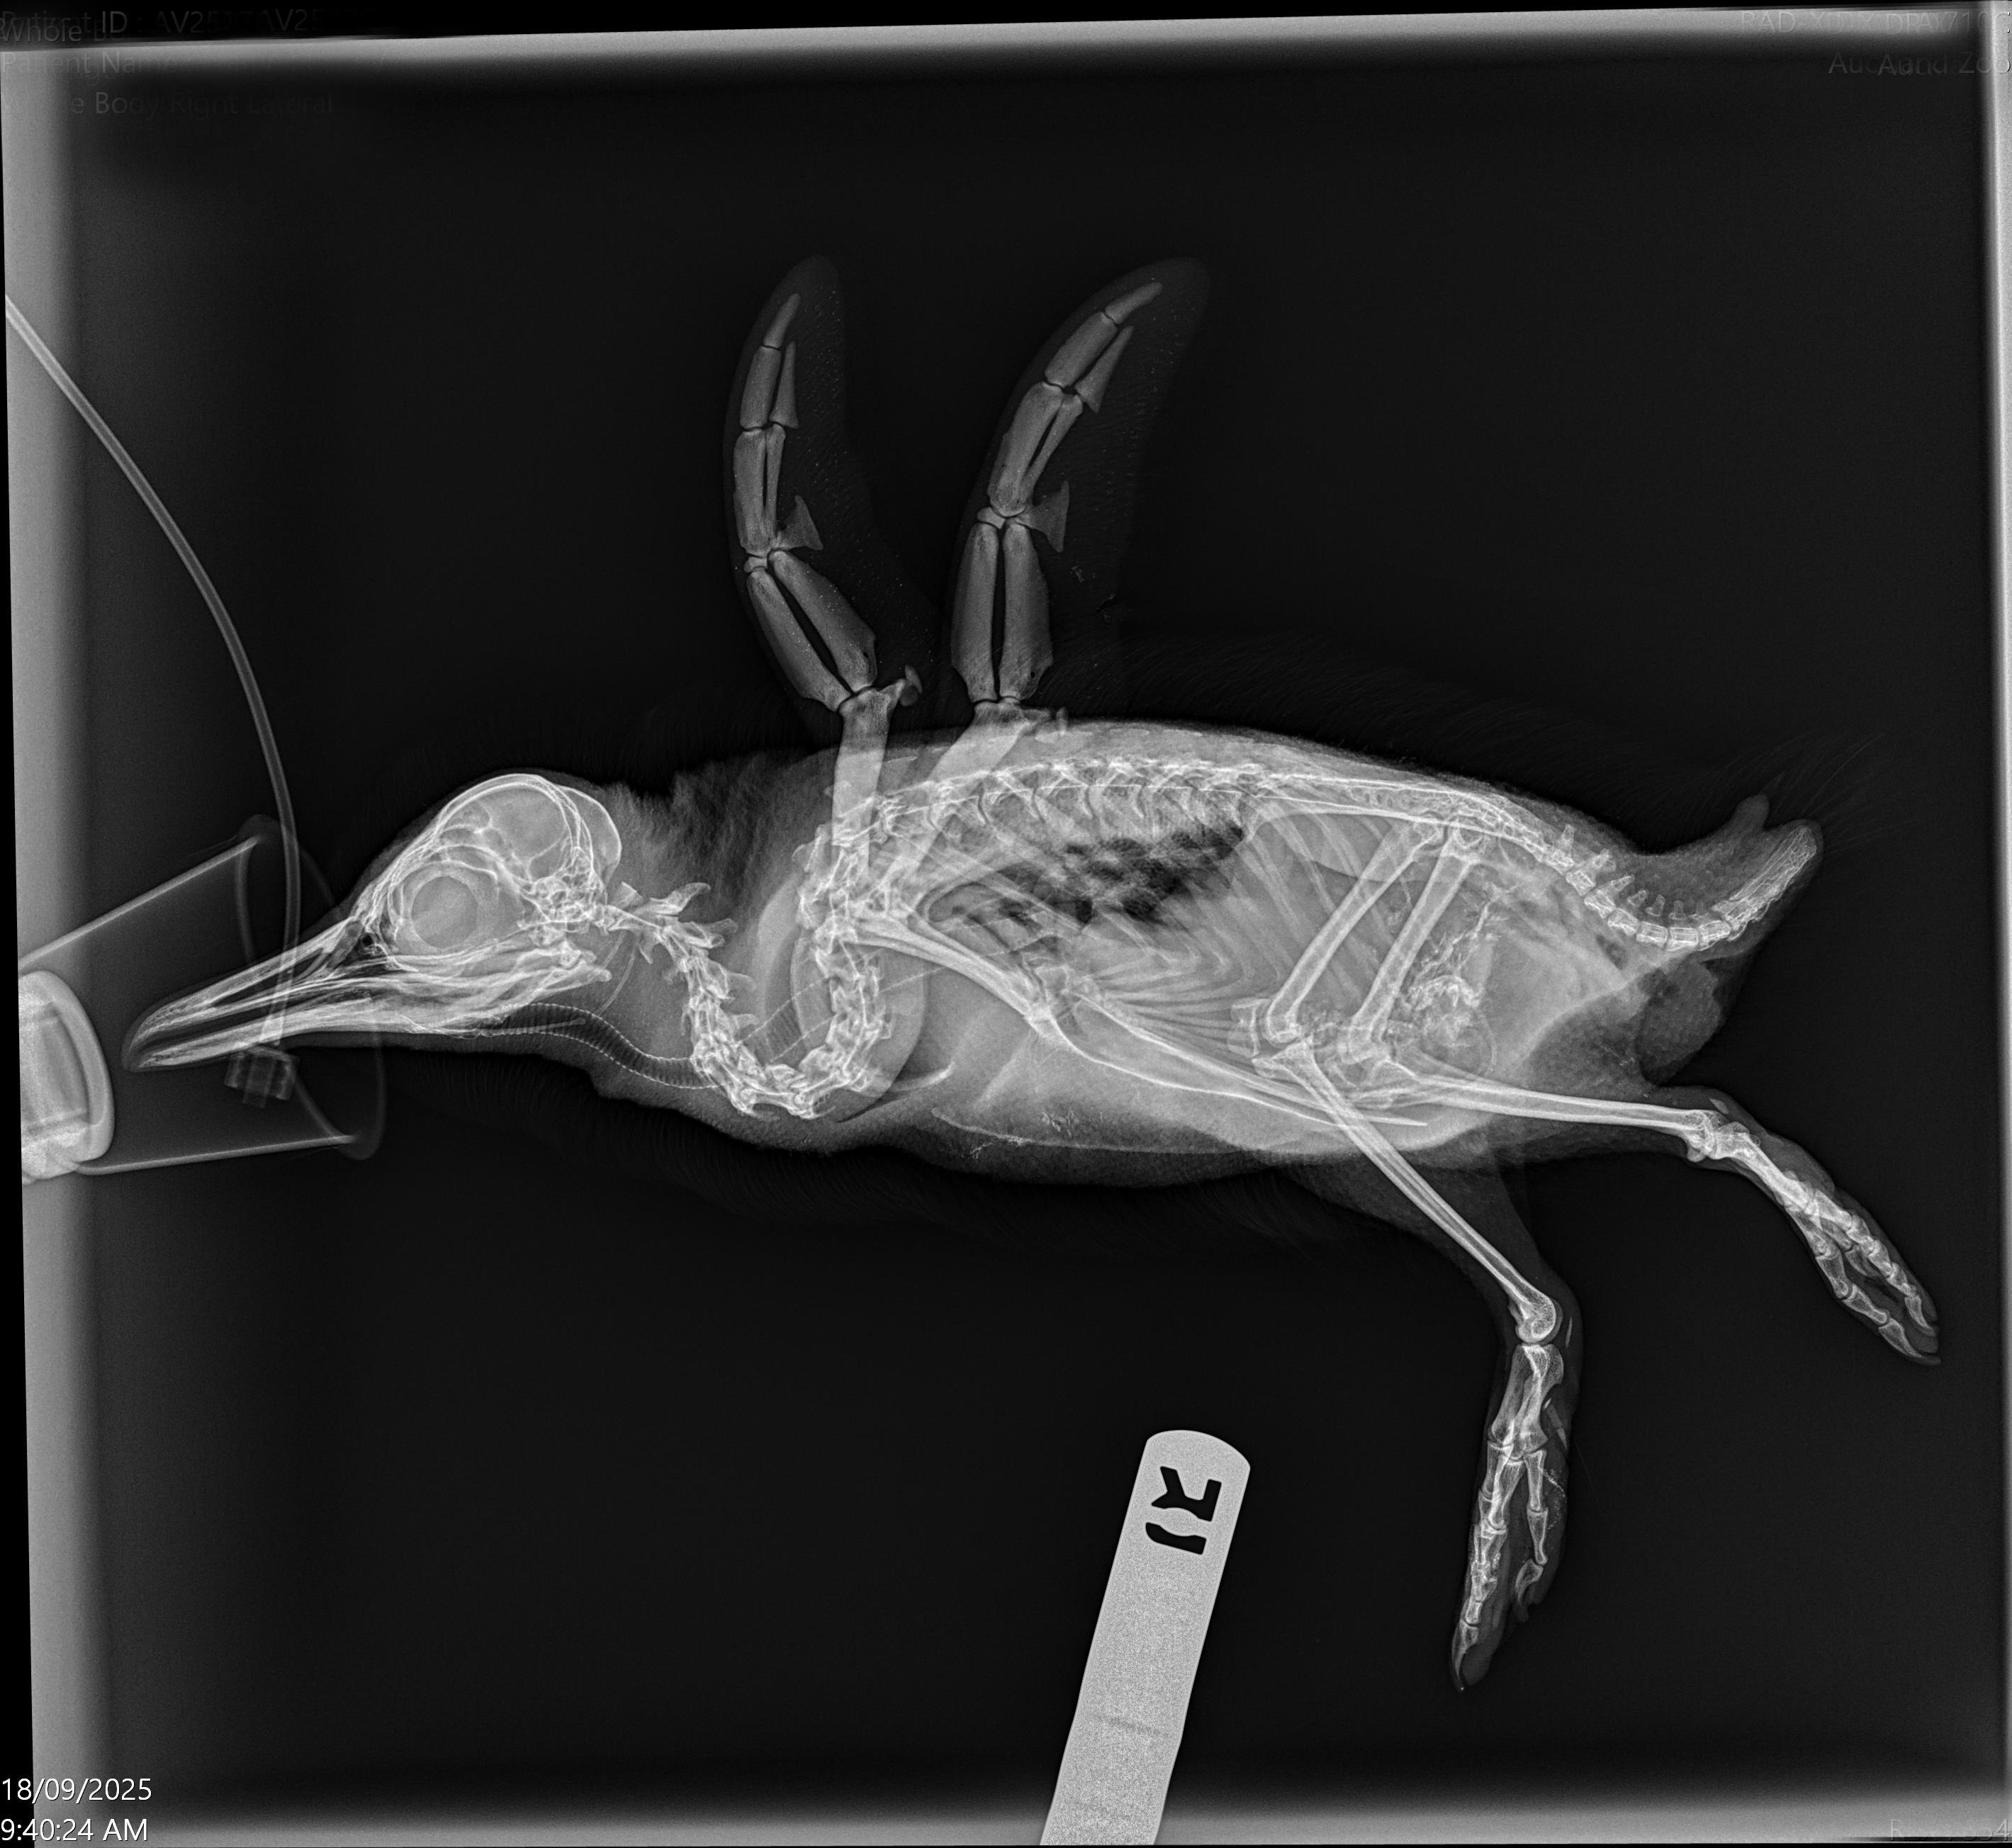

This kororā was very thin on arrival, with wounds on its body and right foot. It immediately received pain relief, antibiotics, antifungals and fluid therapy. Our vet team carried out an initial anaesthetic procedure once the penguin was stabilised, to assess the wounds and take blood tests and X-rays. These blood tests showed inflammation, but its kidneys and liver looked to be okay.

Due to the severity of these wounds and the presence of infection, this patient has needed multiple surgeries. To ensure there was no debris left inside, the wounds were decontaminated and debrided before stitching them up. The deepest part of the wound on the body was right up against the ribs, so we’re thankful for the penguin that it wasn’t any deeper.

Despite antibiotics, the wounds on the right foot developed a severe infection of the bone. A sample of the bacteria was taken and grown in the lab to look for antibiotic resistance and guide further treatment. If antibiotics did not work, the infected bone would have needed to be surgically removed. Thankfully, with the change in treatments, we have seen great improvement and the bone is slowly healing! We’re hopeful that over the next few weeks the bone will continue to heal and we can remove the splint which is in place to protect it.